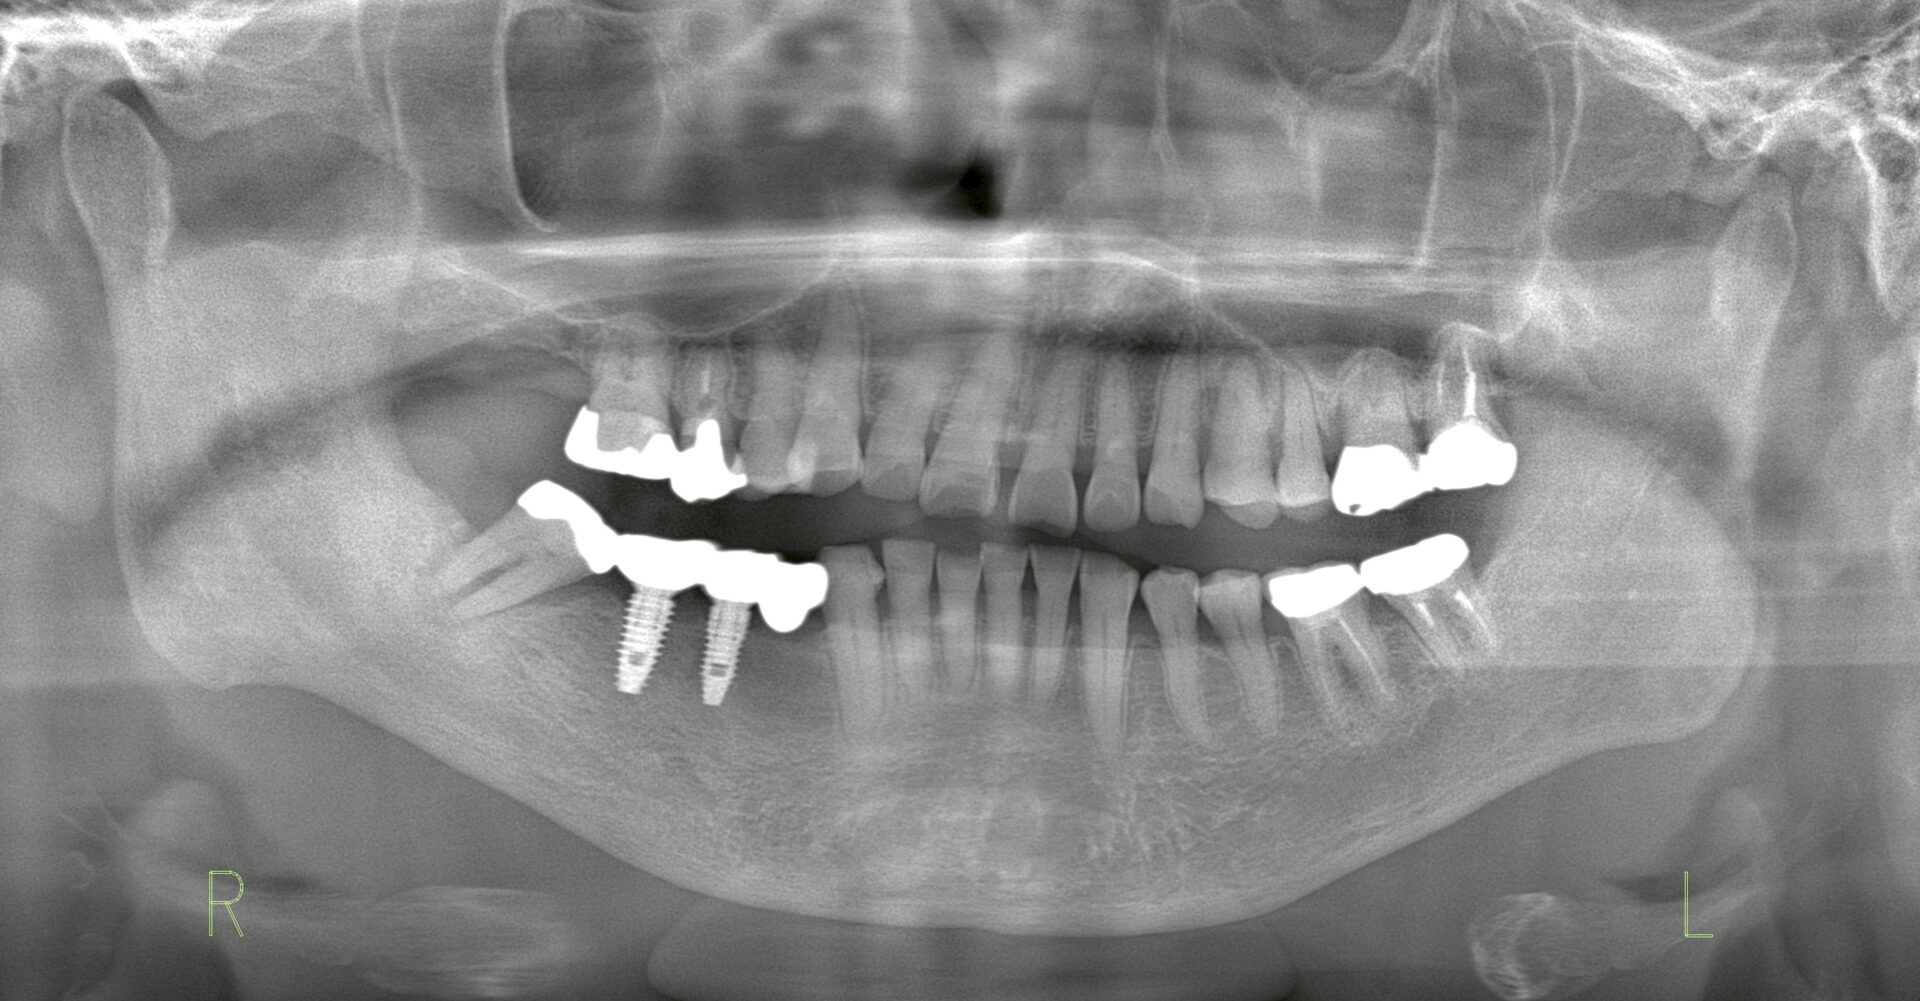

レントゲンの結果、歯根の状態が悪化し病巣が形成されており、抜歯が必要な状態でした。

写真1:術前のレントゲン

写真2:埋入位置を変更したインプラント計画